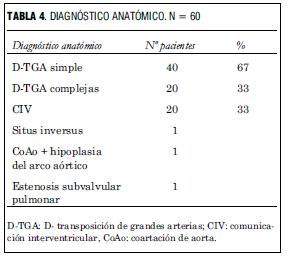

Todos se presentaron con hipoxemia y 25% presentó, además, signos de bajo gasto. Dos tercios eran D-TGA simples y un tercio se presentaron como D-TGA complejas (todas con comunicación interventricular) asociando coartación de aorta e hipoplasia del arco aórtico en un caso, estenosis subpulmonar leve en un caso y situs inversus en un caso. En 76% la distribución coronaria fue tipo A1 de Leiden, en 15% tipo A2 y en 9% para los tipos restantes. Todos recibieron prostaglandina E1 y fueron sometidos a Rashkind. En cuatro casos fue necesaria la administración de óxido nítrico para lograr una saturación adecuada. A todos se les practicó la cirugía de switch arterial.

El análisis anatómico destaca que 40 pacientes presentaron D-TGA con séptum interventricular intacto y 20 con comunicación interventricular. Uno de estos pacientes asoció una coartación de aorta con severa hipoplasia del arco aórtico, otro era portador de un situs inversus (figuras 2 y 3), y otro presentaba una estenosis subpulmonar leve (tabla 4, figura 4).